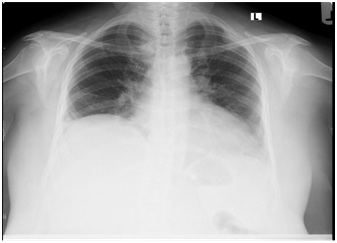

Idiopathic Right Diaphragm Paralysis

Yash H Dubal , et al

Annals of Case Reports